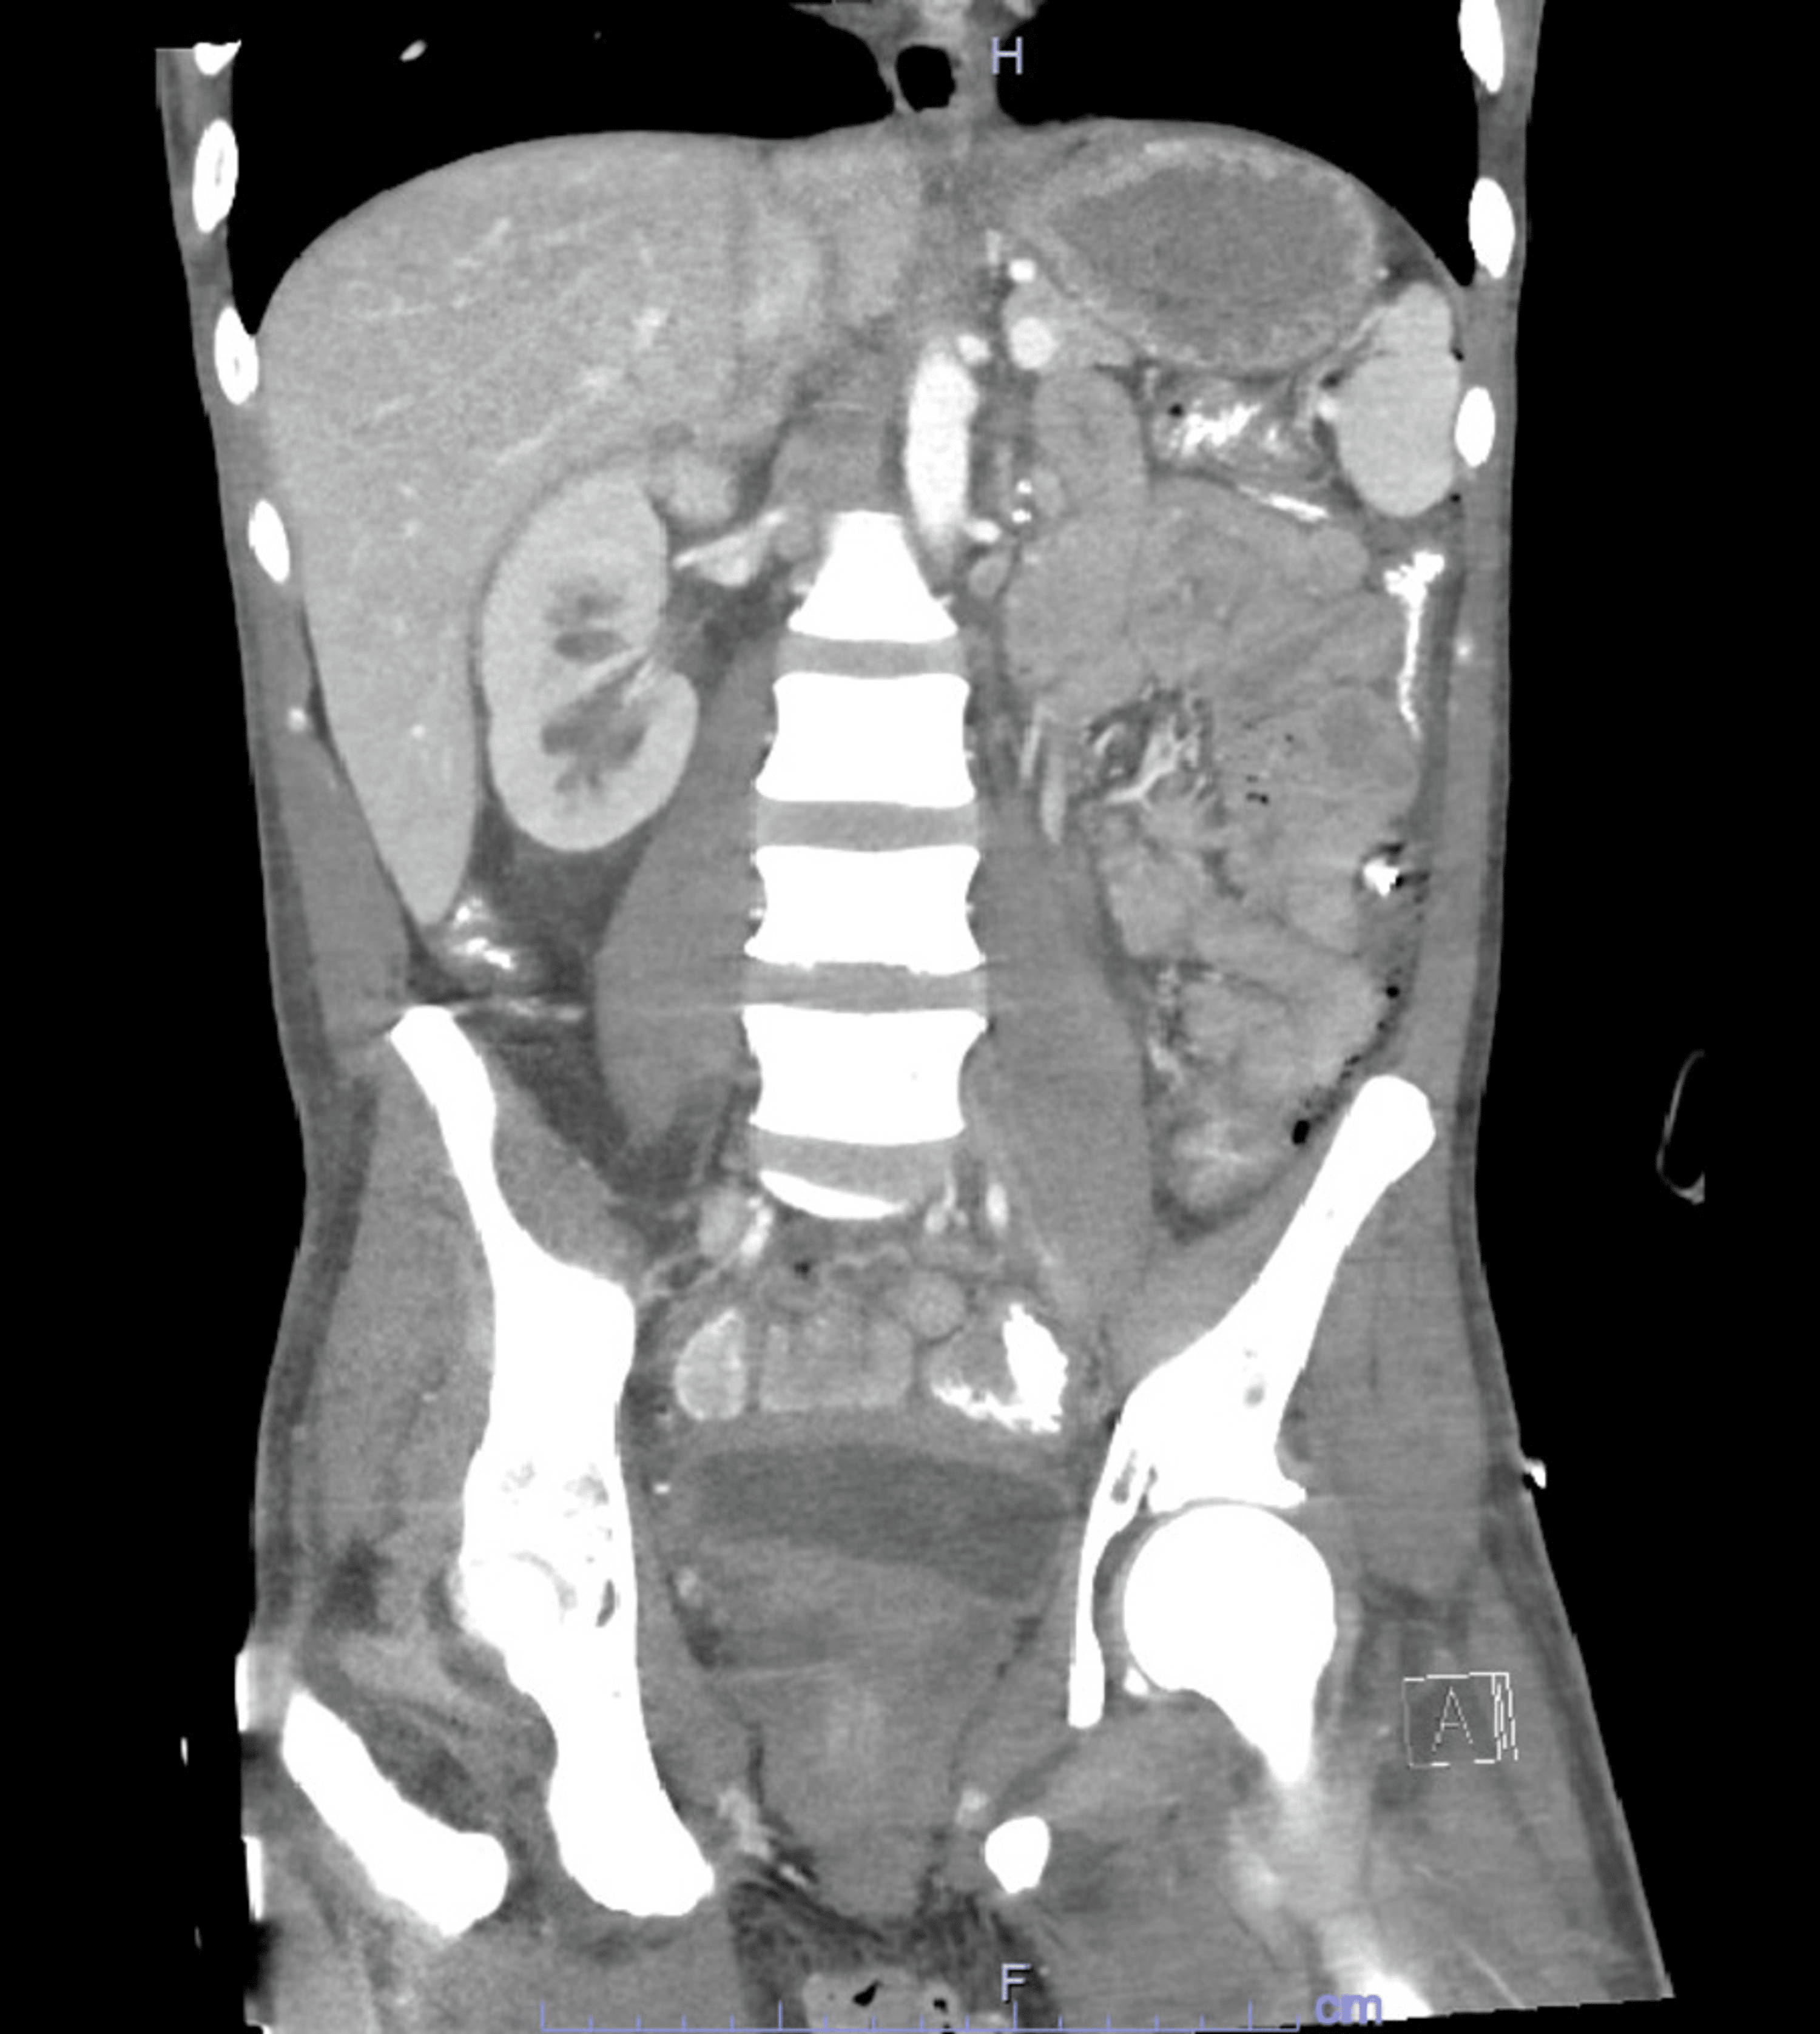

Urinoma postnephrostomy Image

Urinoma postnephrostomy Image Post Nephrostomy The nephrostomy tube drains urine from your kidney into a collecting bag outside your body. Find out how a nephrostomy is done, possible complications and ways to cope with having one. Percutaneous nephrostomy tube placement is a procedure that decompresses or provides access to the renal collecting system in. Willard goodwin in 1955 as a minimally. Blockages can be caused. Post Nephrostomy.